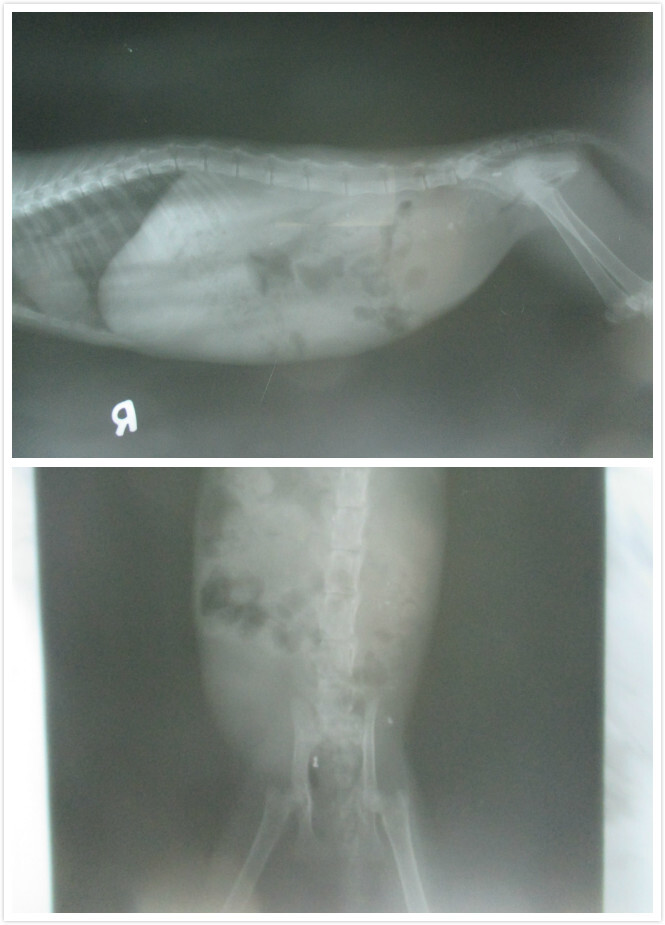

隔天一早送小貓咪去醫院~~目前小貓的狀況後腳癱瘓拖行,背部有傷口且化膿,初步已先鎮定清創並上點滴給予藥物及輸液治療,

脊椎神經有受傷,驗血結果白血球數過高,貓愛滋陽性動物近況說明: 2-23過去看癱瘓小貓咪的狀況

詢問了一下醫生小貓咪的狀況~小貓咪身上的傷口比較不像被狗咬的~畢竟只有一個傷口~也不像被撞的~如果是被撞~畢竟是小貓~一定更嚴重~醫生猜測比較像是自己去撞到尖銳的東西而造成的傷口~而有去傷到神經造成癱瘓~目前有照X光~目前沒斷裂的狀況~傷口應該至少3~4天了~有化膿現像~所以先投抗生素治療~傷口好多了在來看神經方面是否有修復希望~因為送醫那天有看到小貓有自己稍微用後腳支撐一下~